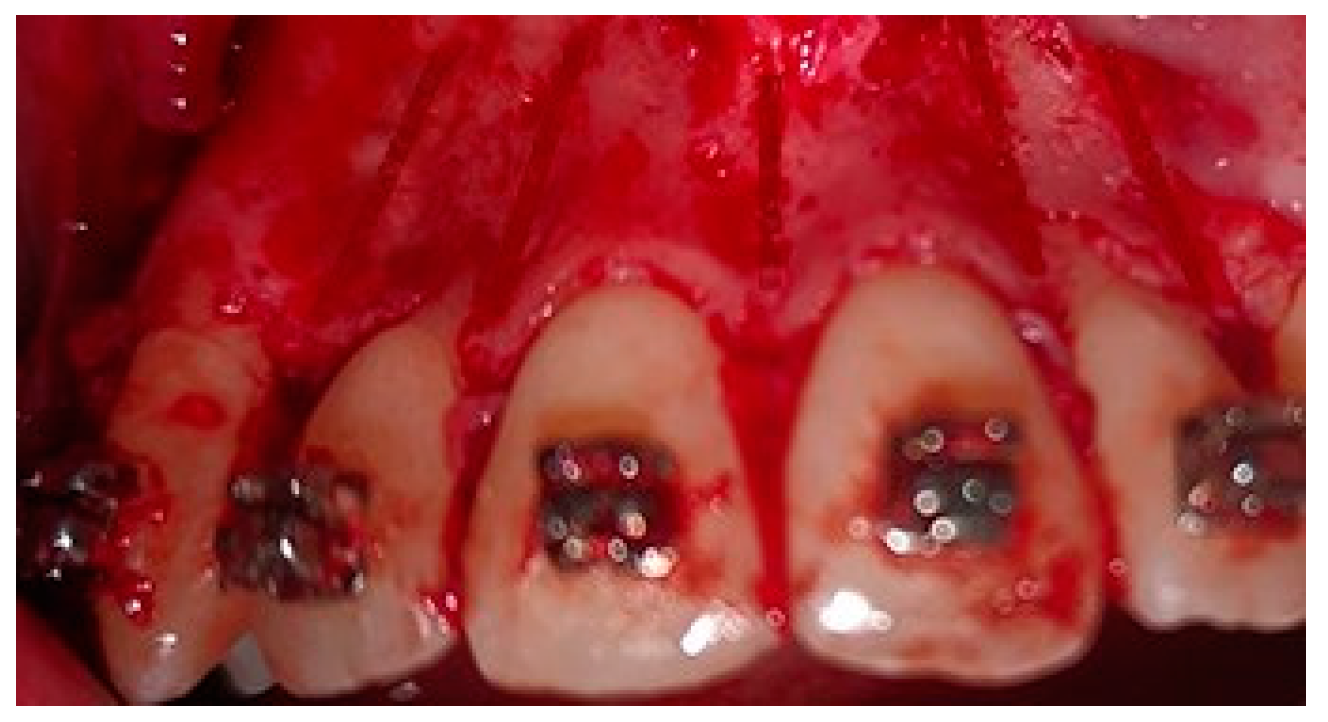

2.5. Surgical Phase

2.6. Collection of the Radiological Data